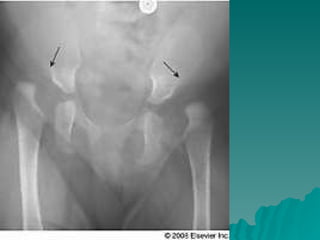

Developmental dysplasia of the hip is a condition where the hip joint is unstable or partially dislocated. It affects 1-50 out of every 1000 live births, with 60% being detected by 1 week of age and 90% by 8 weeks. The document discusses the anatomy, aetiology, pathology, clinical features, imaging, and different treatment approaches depending on if the patient is under 6 months, 6 months to 6 years, or above 6 years of age.